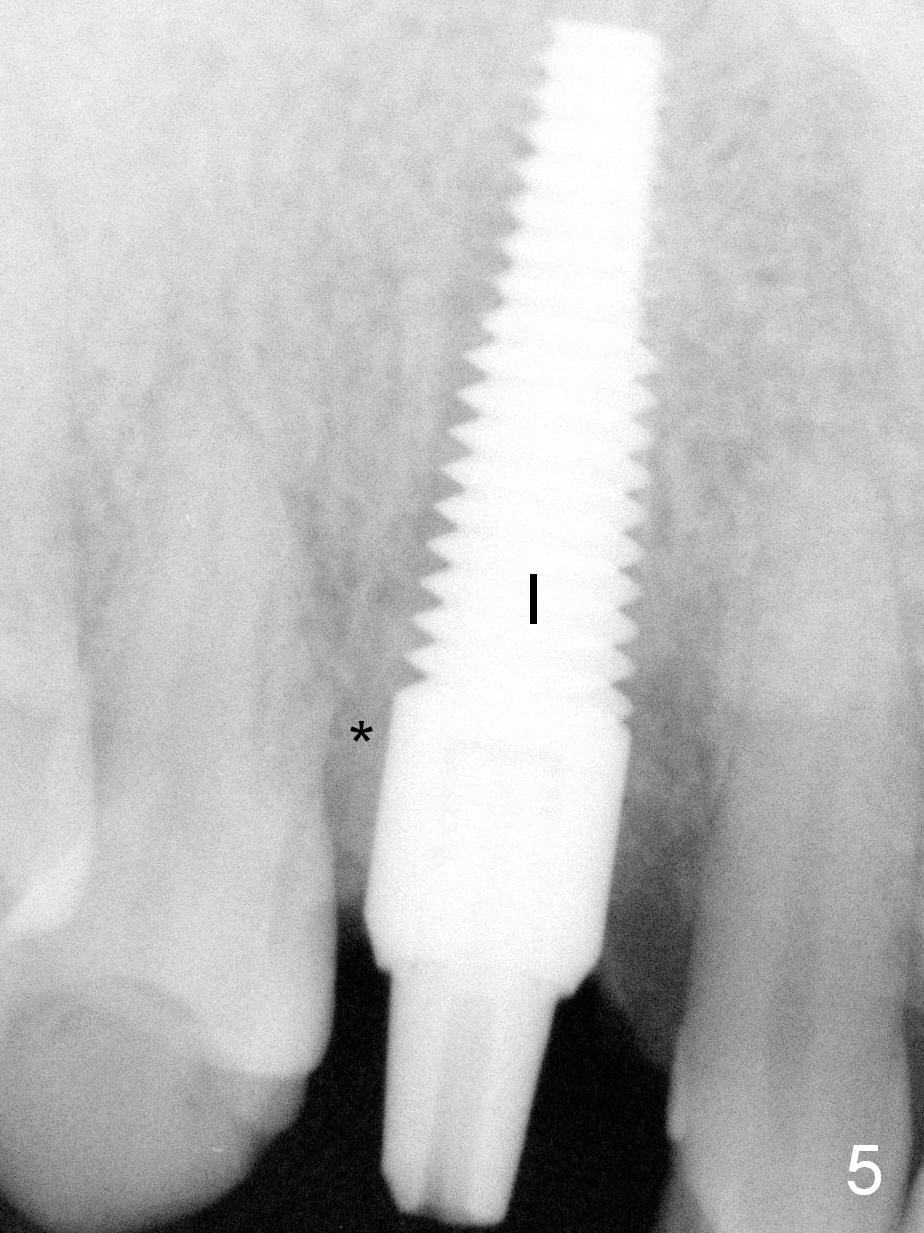

After a 5x20 mm implant (Fig.5 I) is placed, the distal gap is filled with bone graft (*).